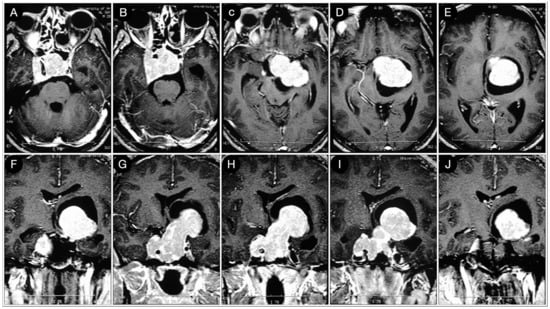

3.3.2. Case #5: Extension beyond the Lateral Wall of the Cavernous Sinus

3.3.3. Case #6: Encasement of the Posterior Communicating and Anterior Choroidal Artery

3.4. Retrosellar Extension

Case #7: Encasement of the Paraclinoid and Supraclinoid Internal Carotid Artery

3.5. Arterial Encasement